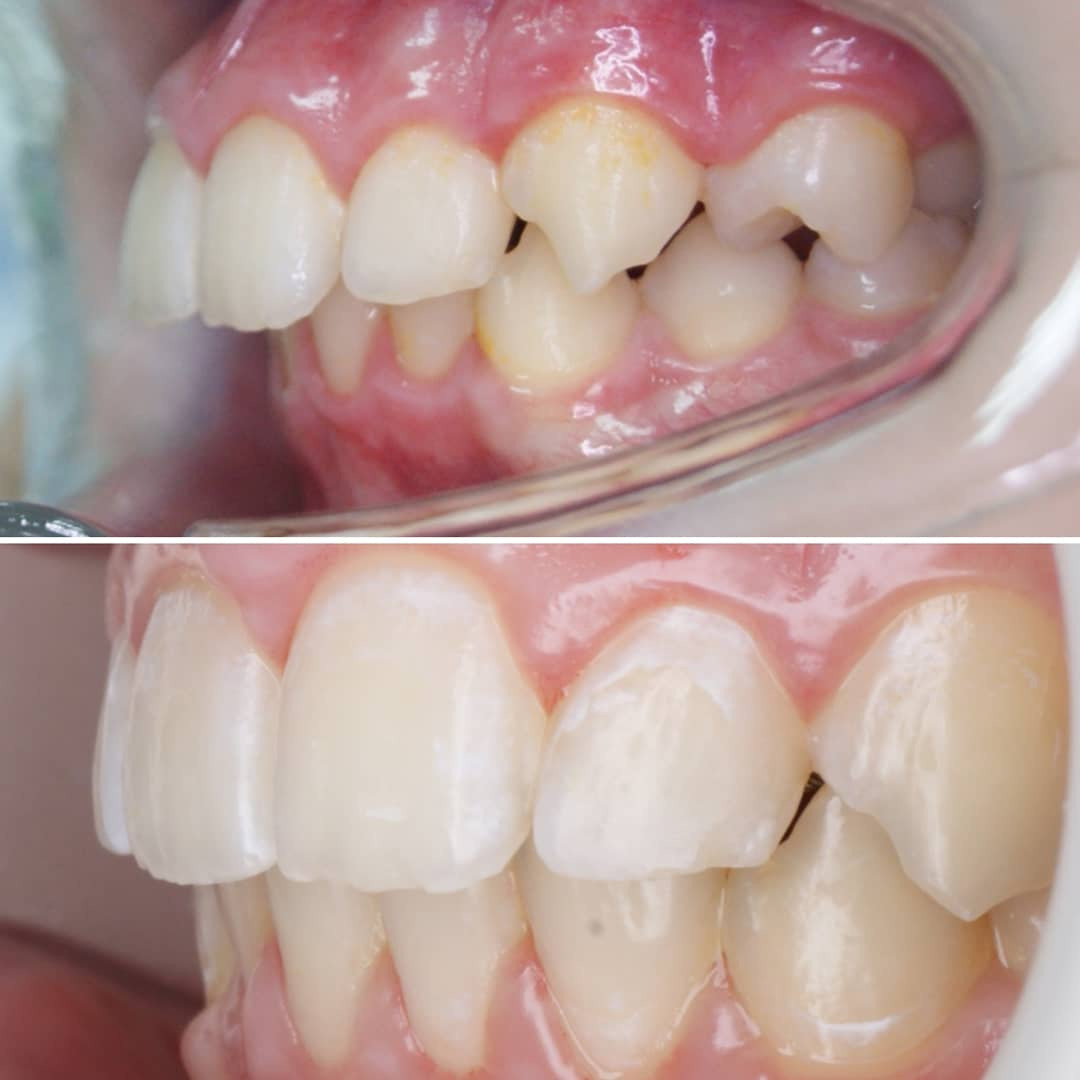

Клинический случай закончен отлично, а вот НЕСОБЛЮДЕНИЕ ГИГИЕНЫ во время ортодонтического лечения привело к изменению эмали зубов!

❗Будьте ответственны к своему здоровью! Соблюдайте гигиену полости рта!❗

Дома с ORMCO. Марафон прямых эфиров👍

✔Во время длительного ортодонтического лечения гигиена затруднена из-за наличия во рту брекетов, дуг, резинок и тд. ✔ Если гигиена не поддерживается на должном уровне, на эмали зубов образуется начальный кариес в виде белых (желтоватых) пятен, который может превратиться в полости или “дырки” (на левой фотографии).✔ Обращаю Ваше внимание, что брекеты зубы не портят! Отсутствие гигиены портит зубы! ✔На правой фотографии современное решение этой проблемы – лечение кариеса без сверления, метод инфильтрации кариеса ICON.

✔Хочу показать жизнь без прикрас ✔Отсутствие должной гигиены во время лечения, которое привело к гингивиту (воспаление десен) и начальной стадии кариеса (меловидные пятна на эмали зубов) ☑Этим постом хочу призвать всех брекетоносцев собдюдать правила гигиены ‼Запомните❗Брекеты не портят зубы! ❗Портит зубы отсуствие тщательной регулярной чистки зубов❗ ✅Дайте своему врачу возможность и время сделать вашу улыбку идеальной